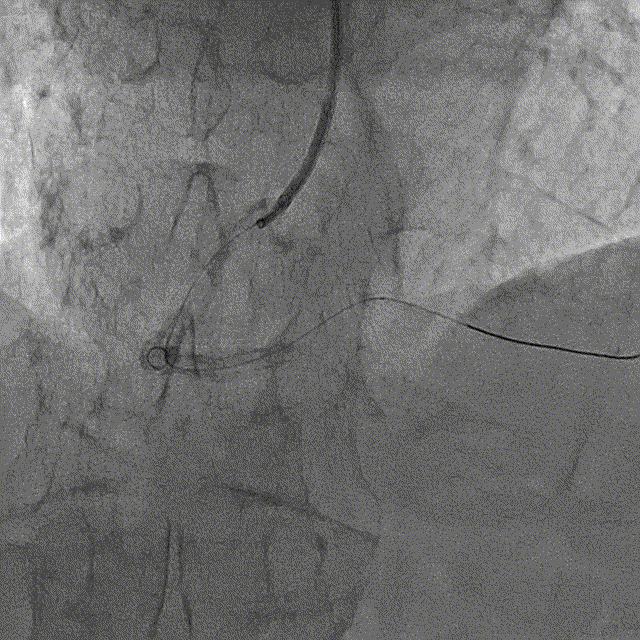

冠脉造影结果:LM外膜钙化,内膜不光滑,中段狭窄90%,TIMI3级。LCX外膜钙化,内膜不光滑,TIMI3级。RCA外膜钙化,内膜不光滑,近段狭窄80%,中段狭窄90%,可见破损斑块,TIMI3级。

冠脉内介入治疗